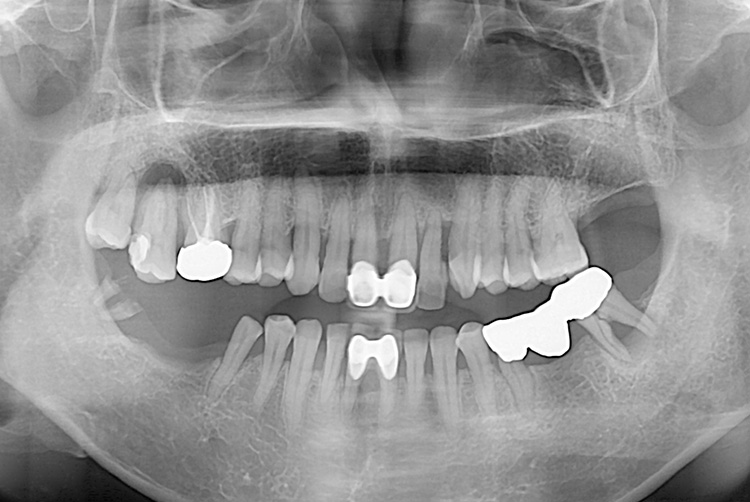

[임플란트] 임플란트

치료전 : 2018-01-08

치료후 : 2020-03-09

세종치과는 많은 환자와 다양한 케이스를 바탕으로 항상 편안한 임플란트 수술을 제공하고자 노력하고,

오래동안 튼튼히 쓸 수 있는 임플란트 수술을 가장 큰 목표로 삼고 있습니다